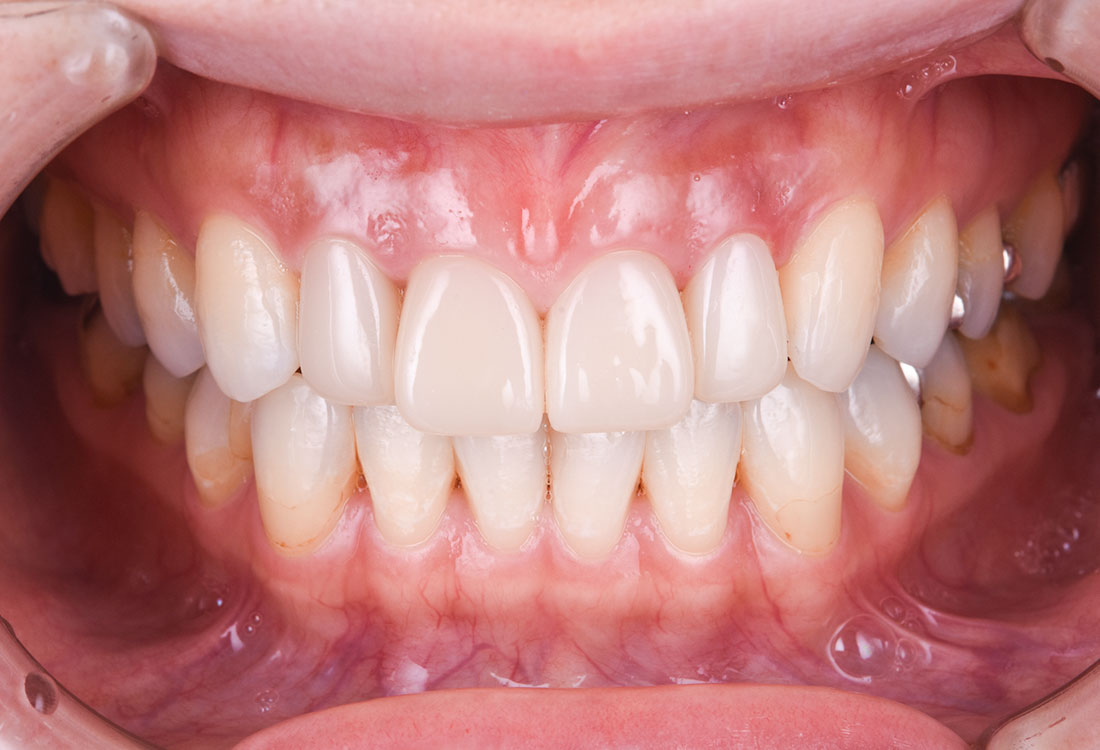

今回は前歯をグラデーションカラーのジルコニア、奥歯をセレックで治療しました。

見た目の美しさのポイントになるスマイルラインも整っています。